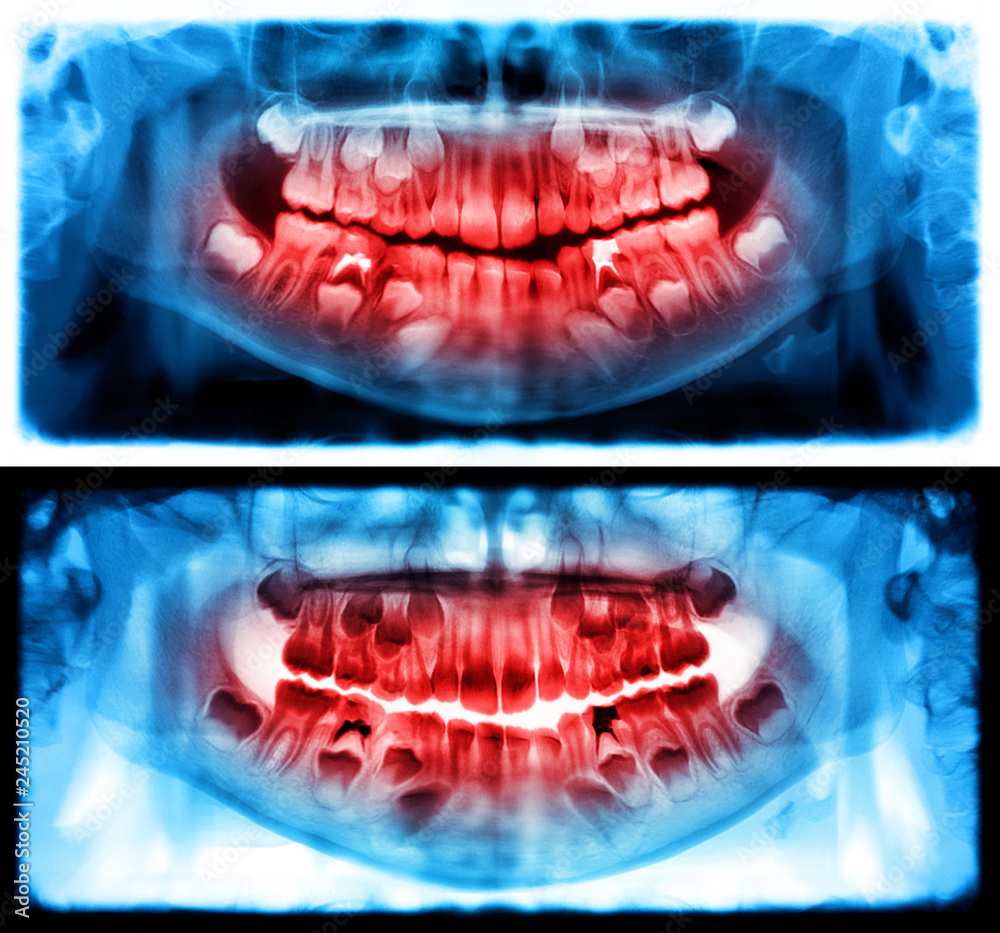

Panoramic radiograph is a scanning dental Xray of the upper jaw Normal Jaw Bone X Ray It occurs when specialized cells, called osteoclasts break down bone tissue and dissolve the bone matrix. The mandible can be considered as an anatomical ring of bone, stabilised at each end at the. This normal physiological process maintains bone remodeling and helps to regulate calcium levels in the body. It is important for radiologists to recognize the indications and appropriate. Normal Jaw Bone X Ray.